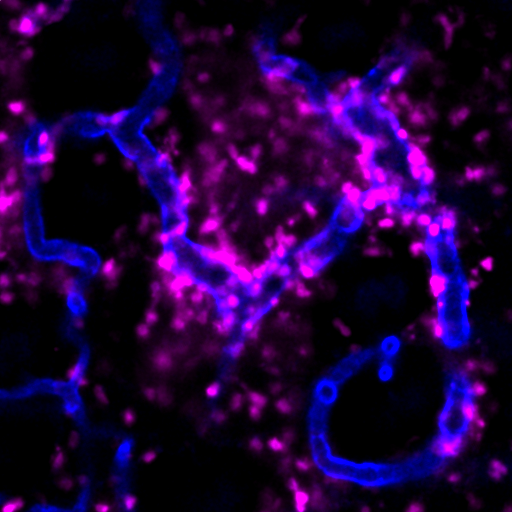

T cells migrating to the lower chamber in the Transwell experiment shown by scanning electron microscopy. -by Quanyin Gu

We systematically investigate the in vivo behavior and fate of drug delivery systems using advanced imaging and analytical tools, including intravital fluorescence microscopy, transmission electron microscopy, and synchrotron radiation-based imaging. Our studies focus on how delivery systems interact with physiological and immune barriers, such as the mononuclear phagocyte system (especially in the liver and spleen), vascular endothelium, and immune cell subsets. We analyze circulation kinetics, biodistribution profiles, cellular uptake mechanisms, and clearance pathways to elucidate the principles that govern delivery efficiency and target-site accumulation. These mechanistic insights guide the rational optimization of carrier design to improve therapeutic precision and minimize systemic toxicity.